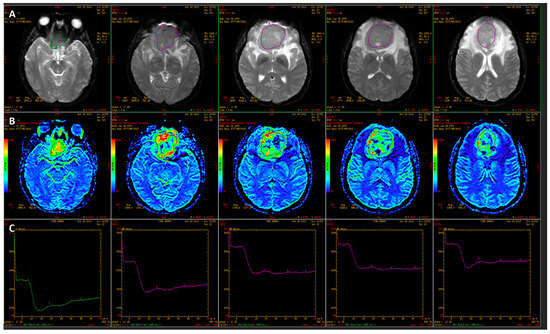

- Korbecki, A.; Machaj, W.; Korbecka, J.; Sobański, M.; Kaczorowski, M.; Tabakow, P.; Hałoń, A.; Trybek, G.; Podgórski, P.; Bladowska, J. Evaluation of the Value of Perfusion-Weighted Magnetic Resonance Imaging in the Differential Diagnosis of Sellar and Parasellar Tumors. J. Clin. Med. 2023, 12, 2957. [Google Scholar] [CrossRef]